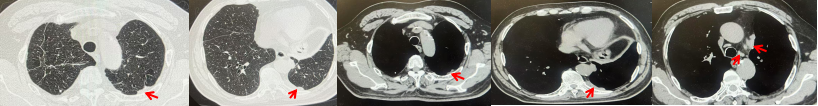

2024.11.19患者出现右侧胸痛,复查胸部CT检查示右侧胸膜肿物,大小约31mmX24mm,右侧4、5肋骨骨质破坏,考虑转移(如图2)。建议患者穿刺活检取病理明确诊断,患者拒绝,经MDT会诊后结合影像学表现及病史考虑为胸膜转移,肋骨转移,分期为rT0N0M1a IVA期,DFS仅仅17个月。2024.12.05起行信迪利单抗联合培美曲塞+卡铂方案治疗4周期,复查胸CT评效PR(如图3)。之后给予信迪利单抗+培美曲塞维持治疗6周期,期间复查CT评效PR(如图3)。目前信迪利单抗+培美曲塞维持治疗中,截止至目前PFS约为8个月,治疗期间未出现明显毒副反应。

图3:患者免疫联合化疗治疗后胸部CT,(A、B)图展示信迪利单抗联合培美曲塞+卡铂治疗

4周期(2025.02)疗效,(C、D)图展示信迪利单抗+培美曲塞维持治疗6周期(2025.07)疗效